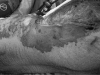

Methods: We describe four cases of monomicrobial and polymicrobial A. baumannii-associated necrotizing SSTI accompanied by A. baumannii bacteremia and offer a review of similar experiences published in the literature.

Results: Our comparative analysis reveals four unique features associated with necrotizing SSTI associated with A. baumannii: i) Occurs in hosts with underlying comorbidities (e.g., trauma, cirrhosis); ii) is often accompanied by bacteremia; iii) multiple drug resistance and the presence of co-pathogens frequently complicated treatment (64% of cases); iv) the cases reported here and in our review required surgical debridement (84% of cases) and led to substantial mortality (approximately 30%).